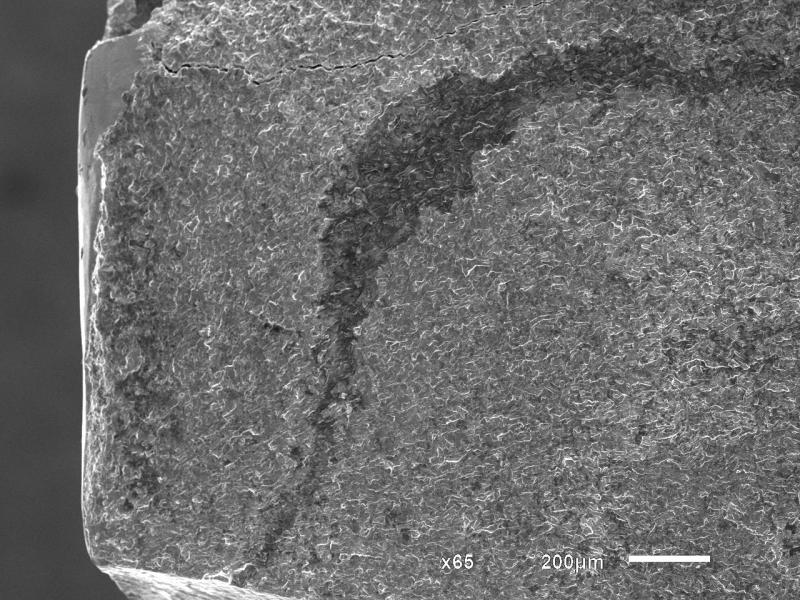

纯钛接骨板断口分析

是纯Ti金属接骨板,在人体内使用6个月后断裂。最后一张图是否为疲劳台阶,我推测为疲劳腐蚀断裂,本人刚开始接触断口,请各位帮忙一起分析断口。

最后断裂位置

心部宏观

心部

心部放大

裂源

台阶是什么??

实物图,箭头为裂源处